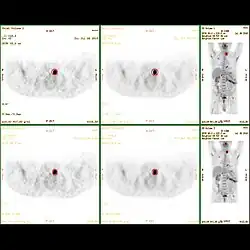

Statische Datenaufnahme

Der am häufigsten angewandte Aufnahmemodus ist die Statische Aufnahme. Hierbei werden alle Ereignisse, die während einer bestimmten Zeitspanne an derselben Aufnahmeposition auflaufen, für die Bildrekonstruktion verwendet. Typischerweise werden pro Aufnahmeposition bei einer FDG-PET Koinzidenzen über eine Zeitspanne von zwei bis vier Minuten akquiriert. Je länger die Aufnahme läuft, desto größer wird die Zahl der für die Bildrekonstruktion verwendbaren Koinzidenzereignisse, was die Bildqualität im Hinblick auf das Signal-Rauschverhältnis verbessert. Eine Verlängerung der Aufnahmedauer vergrößert jedoch andererseits die Wahrscheinlichkeit von Bewegungsartefakten durch willkürliche und physiologische Bewegungen des Untersuchungsobjektes. Eine Statische Aufnahme gibt Aufschluss über die zum Aufnahmezeitpunkt im Untersuchungsvolumen angereicherte Tracermenge. Die Geschwindigkeit der Anreicherung kann damit nicht beurteilt werden, hierfür ist eine dynamische Akquisition erforderlich.